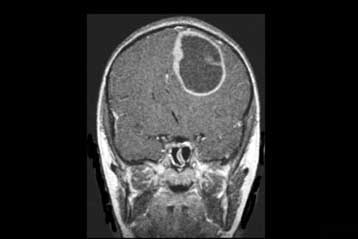

Αθήνα: Δεκάδες χιλιάδες ασθενείς, καταδικασμένοι σε θάνατο ή αναπηρία μετά από εγκεφαλικό η άλλο αγγειακό επεισόδιο, σώζονται πλέον χάρις και στην Ενδαγγειακή Χειρουργική, που άλλαξε τον τρόπο αποκατάστασης των αγγειακών νόσων.